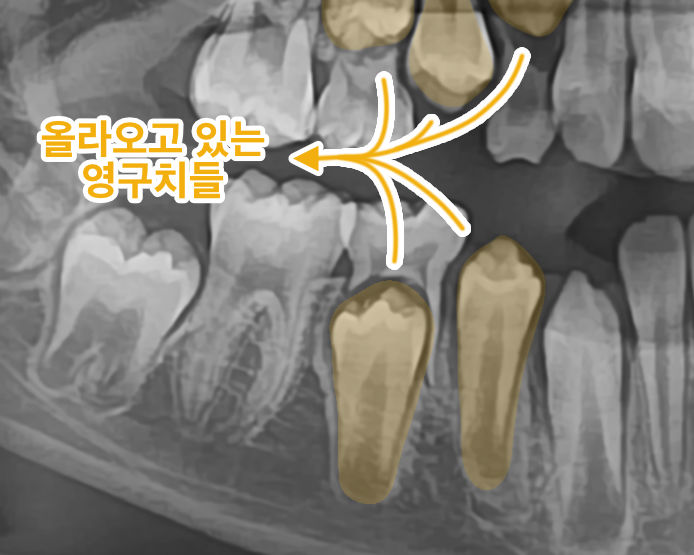

영구치가 얼마나 올라왔나, 유치 뿌리는 얼마나 올라왔나 확인할 수도 있으며